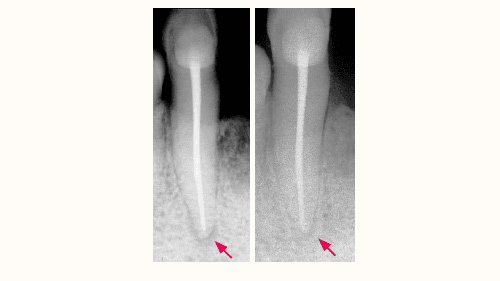

Tand med nervebetændelse (venstre) og tand med rodspidsbetændelse (højre).

Kilde: tandlægeforeningen